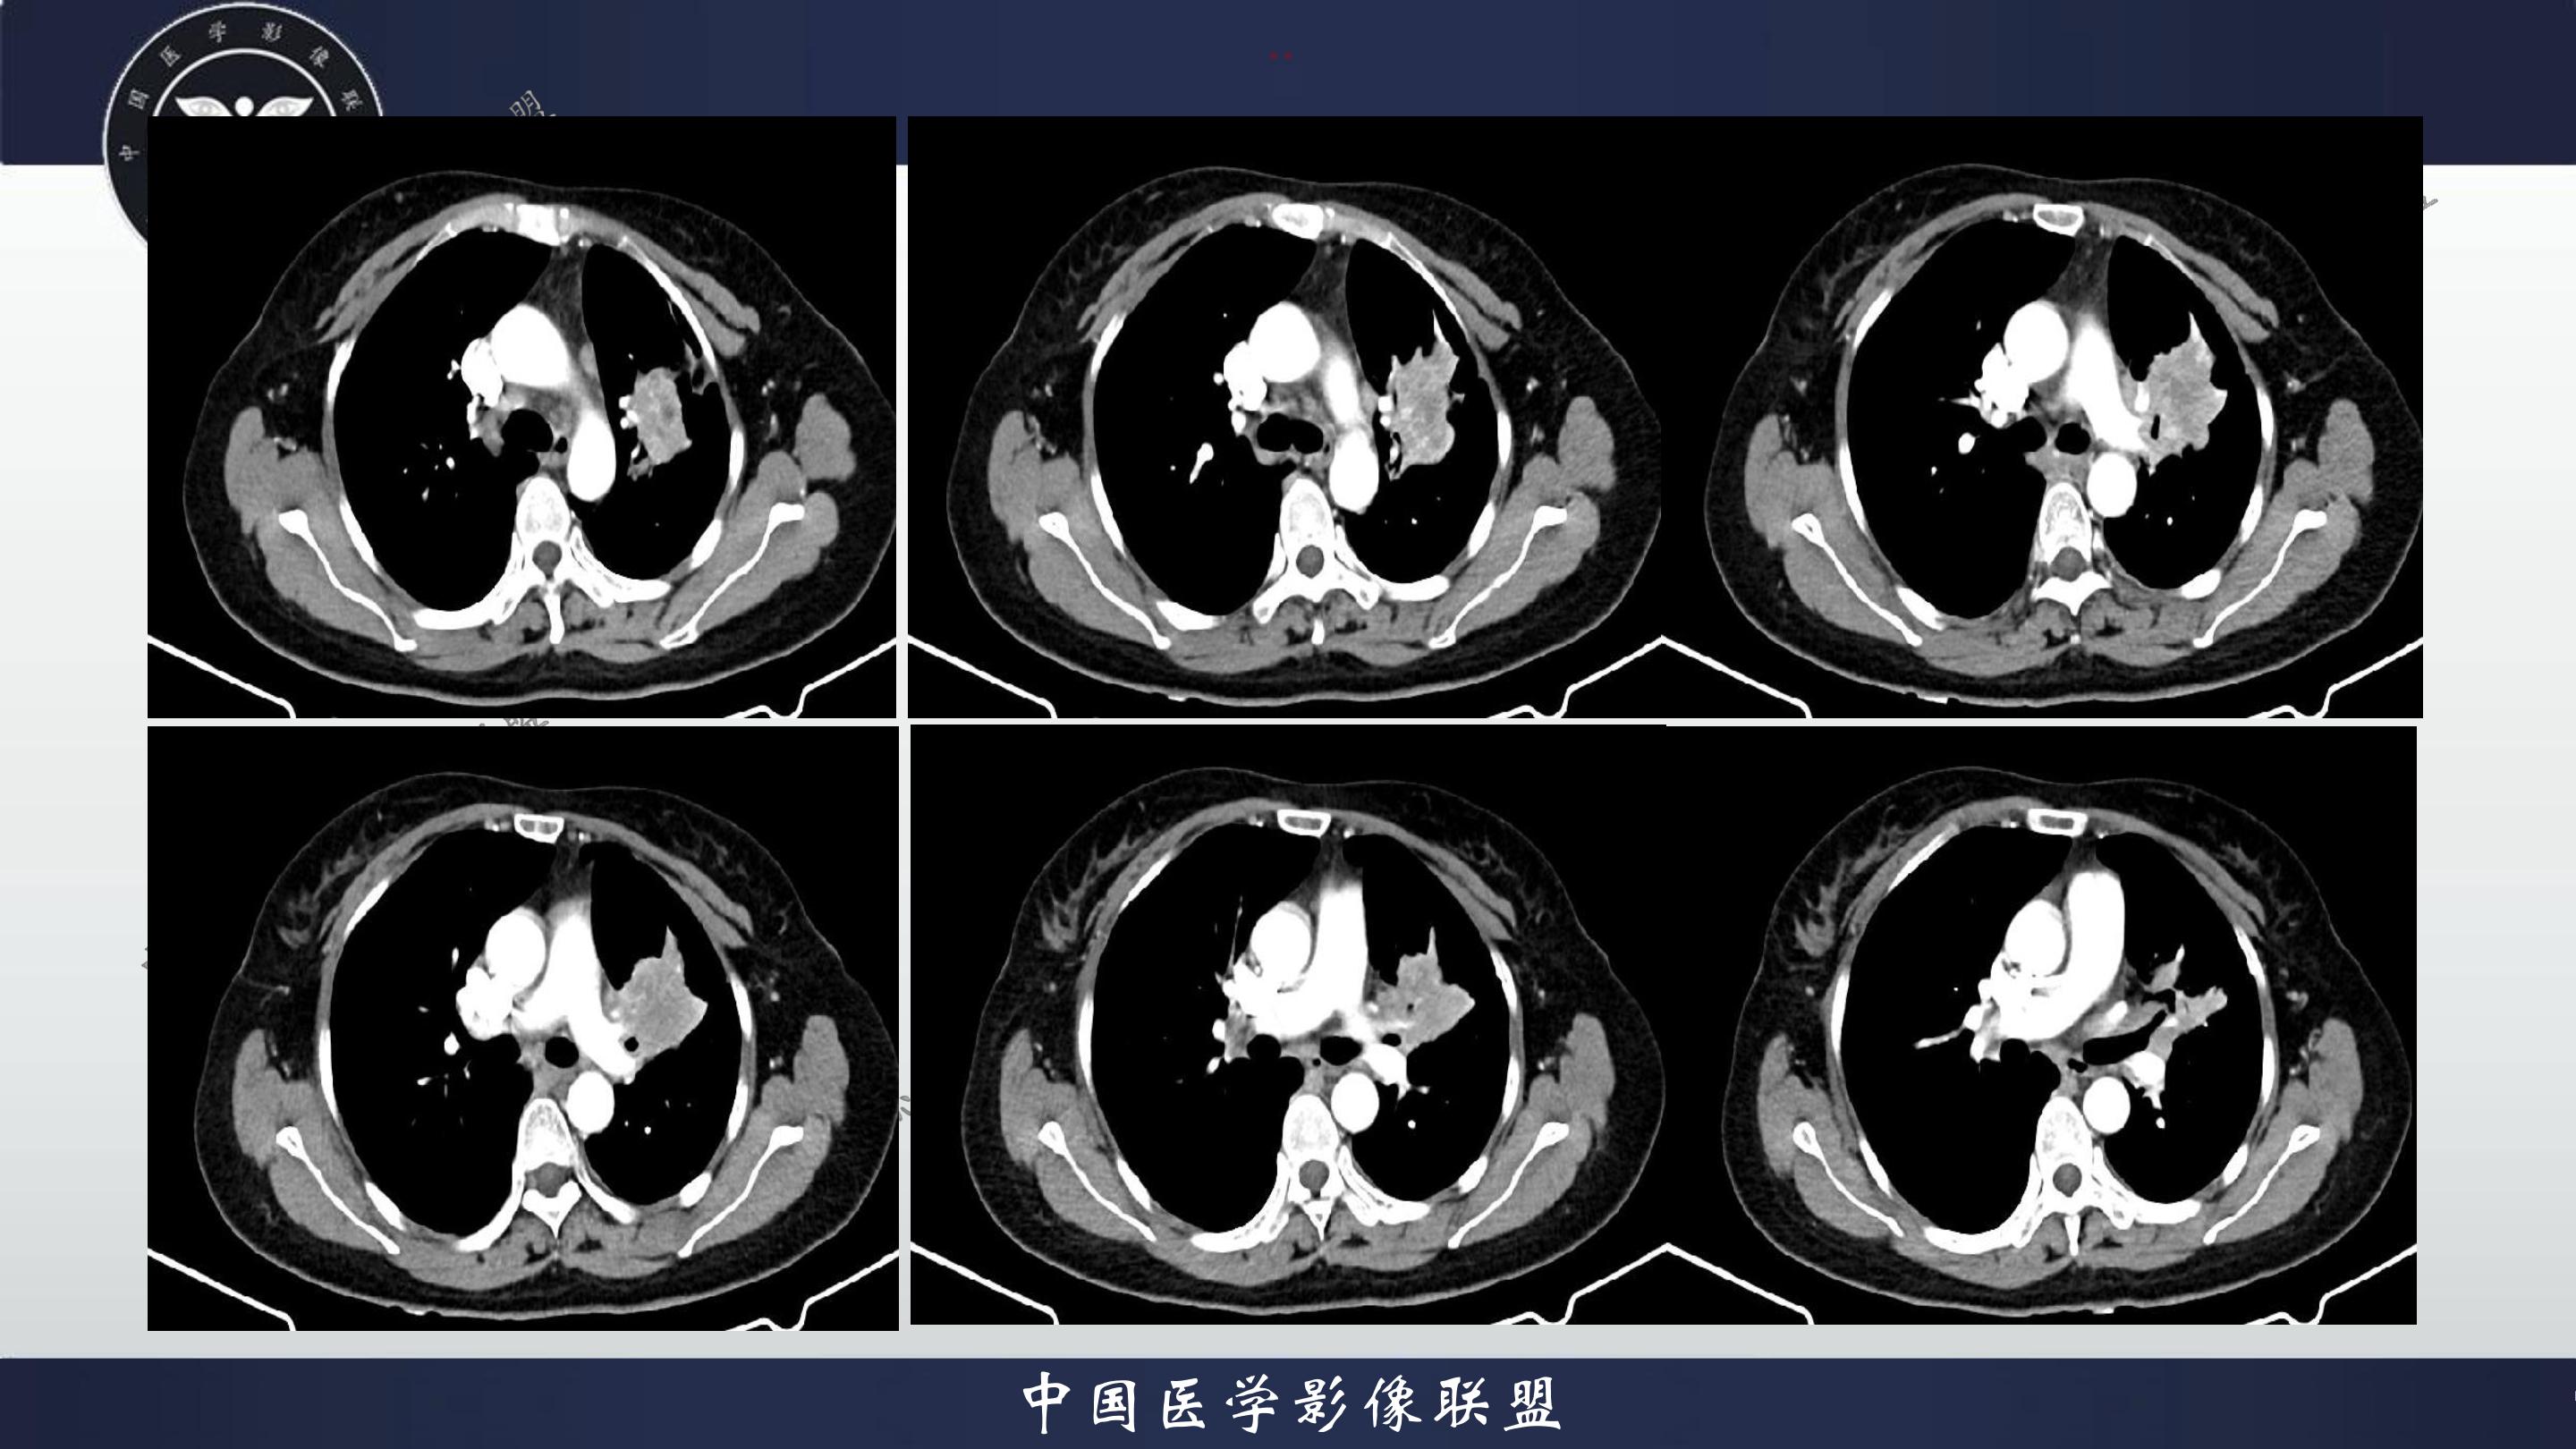

老年女性,咳嗽、咳痰伴痰中带血3月

3月前患者无明显诱因出现咳嗽、咳痰,呈阵发性咳嗽,咳大量黄色脓痰,痰不易咳出,伴痰中带血,量少,具体量不详,伴鼻塞、口干、乏力,活动后感喘息、劳累,休息后缓解,无发热、畏寒,无盗汗,无心慌、胸闷,无腹痛、恶心、呕吐,无头昏、心前区压榨性不适,院外予以输液及口服药物治疗后症状无明显缓解,现为系统诊治就诊我院门诊,门诊以“社区获得性肺炎”收入我科。病来精神、饮食、睡眠尚可,大小便正常,体重无明显变化。

既往有高血压病史10+年,血压最高160/70mmhg,自诉长期口服降压药物治疗,具体药物名称不详;8+年前患者有胆囊结石病史,自诉当时予以手术治疗后好转出院,具体不详;否认“糖尿病、冠心病"等疾病史。否认“肝炎、伤寒、结核”等传染病史;否认已知药物及食物过敏史,否认烟酒史

查体:T:36.8℃P:82次/分,R:20次/分,BP:135/82mmHg,spo2:96%.神清合作,咽稍充血,双侧扁桃体无肿大;双肺呼吸音粗,双肺可闻及少许湿性啰音,未闻及哮鸣音;心界不大,心率82次/分,律齐,心音低钝,各瓣膜听诊区未闻及杂音,腹软,中上腹压痛,无反跳痛及肌卫,肝脾未扪及。双下肢无水肿。

4.辅查:生化报告(2024-11-14 13:06:51)尿素氮或尿素:10.1mmol/L↑,尿酸:342umol/L↑,钾离子:3.16mmol/l↓,尿常规报告(2024-11-14 13:11:41)隐血:+2,凝血报告(2024-11-14 13:16:37)血浆D-二聚体测定:0.62ng/mL↑,生化报告单(2024-11-14 16:14:45)MP滴度(1:40):弱阳性,PCR报告(2024-11-14 16:50:37)人鼻病毒核酸(HRV-RNA)定性:阳性,传染性指标、粪便常规、BNP、心肌特异蛋白、CEA、肝功能、血脂、红细胞沉降率未见明显异常。血气分析回示:PH 7.443 PCO2 28.3mmhg PO2 90.9mmhg HCO3- 19.53mmol/L 氧和指数432.9mmhg;心电图回示:1.窦性心律2.T波改变(Ⅲ倒置、aVF低平)